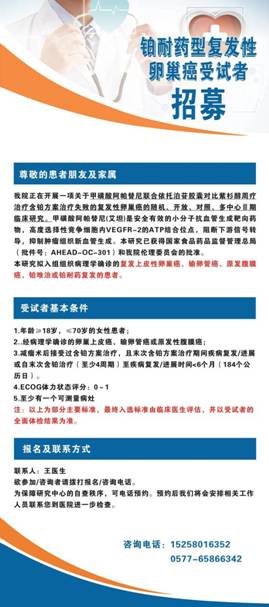

目前我科已对接了多个国内、国际多中心药物临床试验,主要集中在免疫、抗血管生成、多靶点小分子TKI抑制剂等新药,涵盖卵巢癌、结直肠癌、小细胞肺癌等多个瘤种,为肿瘤初治或者是多线治疗失败的患者提供更多治疗选择,提高疗效的同时可大大减轻患者的经济负担。

下图为我科对接临床试验的具体入组要求,如有需求可携带相关资料赴肿瘤内科门诊了解。